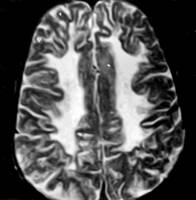

Modificari precoce in boala sunt cosiderate aparitia zonelor de hipersemnal, definitorii, pe imaginile cu predominanta T2 (fig. 2), cu precadere la nivelul substantei albe subcorticale occipitale mai mult decat a celei frontale. In majoritatea cazurilor, substanta cenusie este integra, chiar si in cazurile avansate.

Figura 2: imagine prin rezonanta magnetica avand

predominanta T2, prezentand demielinizare difuza a

substantei albe, la un baiat in varsta de 8 ani, cu PESS.